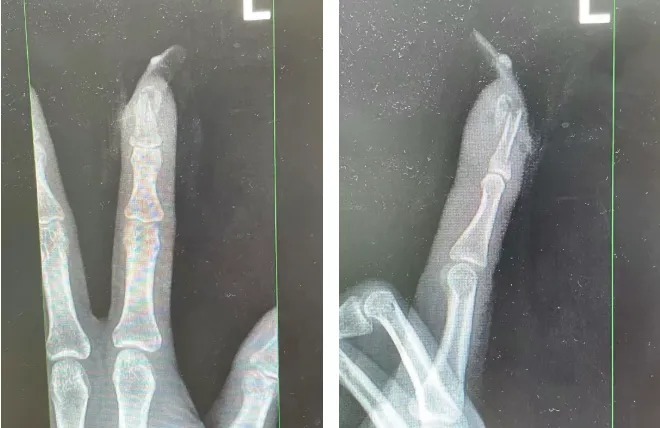

图片

王女士受伤手指的X光影像。图源:杭州市临平区中西医结合医院